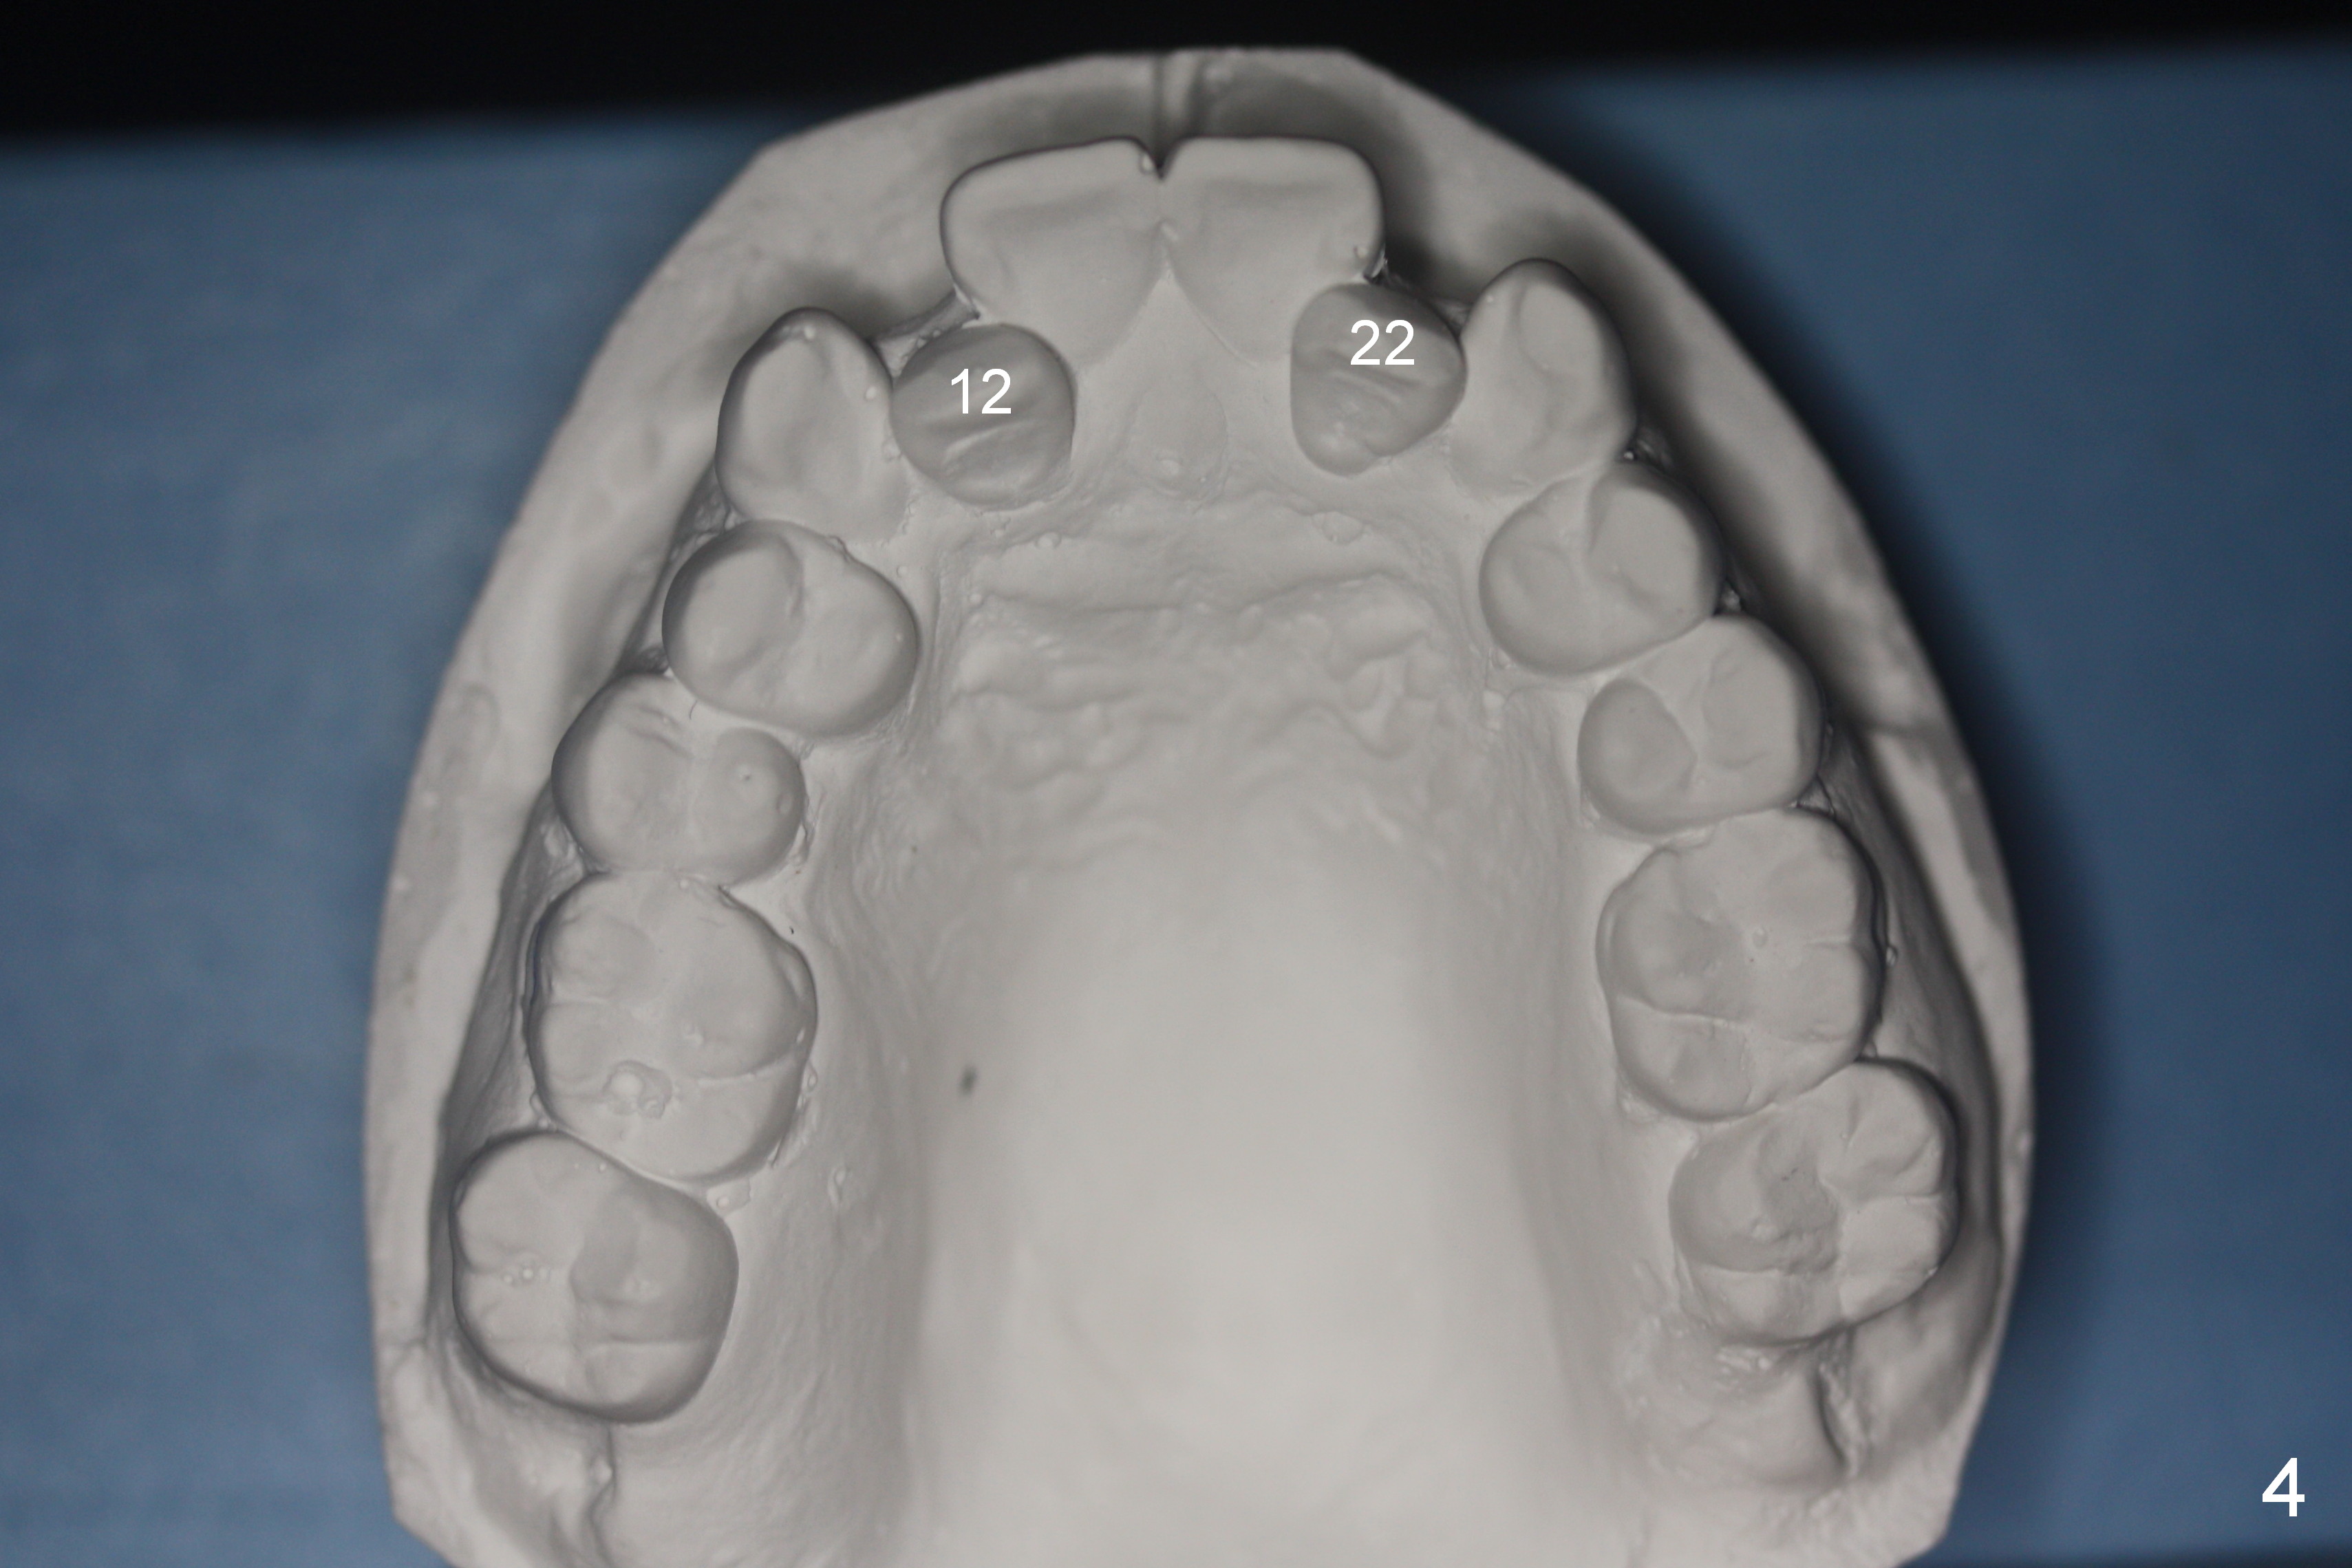

A 37-year-old man requests orthodontic treatment for severe crowding with 3 blocked-out incisors (Fig.1-5: 12,22,31 (International numbering, pronounced one two, two two and three one)). The upper and lower arches are pointed (Fig.4,5). The best option is extraction of 4 bicuspids (Fig.11-15).